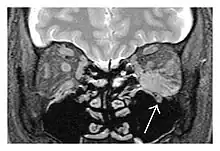

The extent of inflammation that can occur in IgG4-ROD is well demonstrated on magnetic resonance imaging (MRI).

![]() Bilateral supraorbital nerve enlargements (arrows) and right infraorbital nerve (arrow head) enlargement in a 47-year-old woman with a serum IgG4 of 1000 mg/dL.[1] (T1-weighted MRI) |